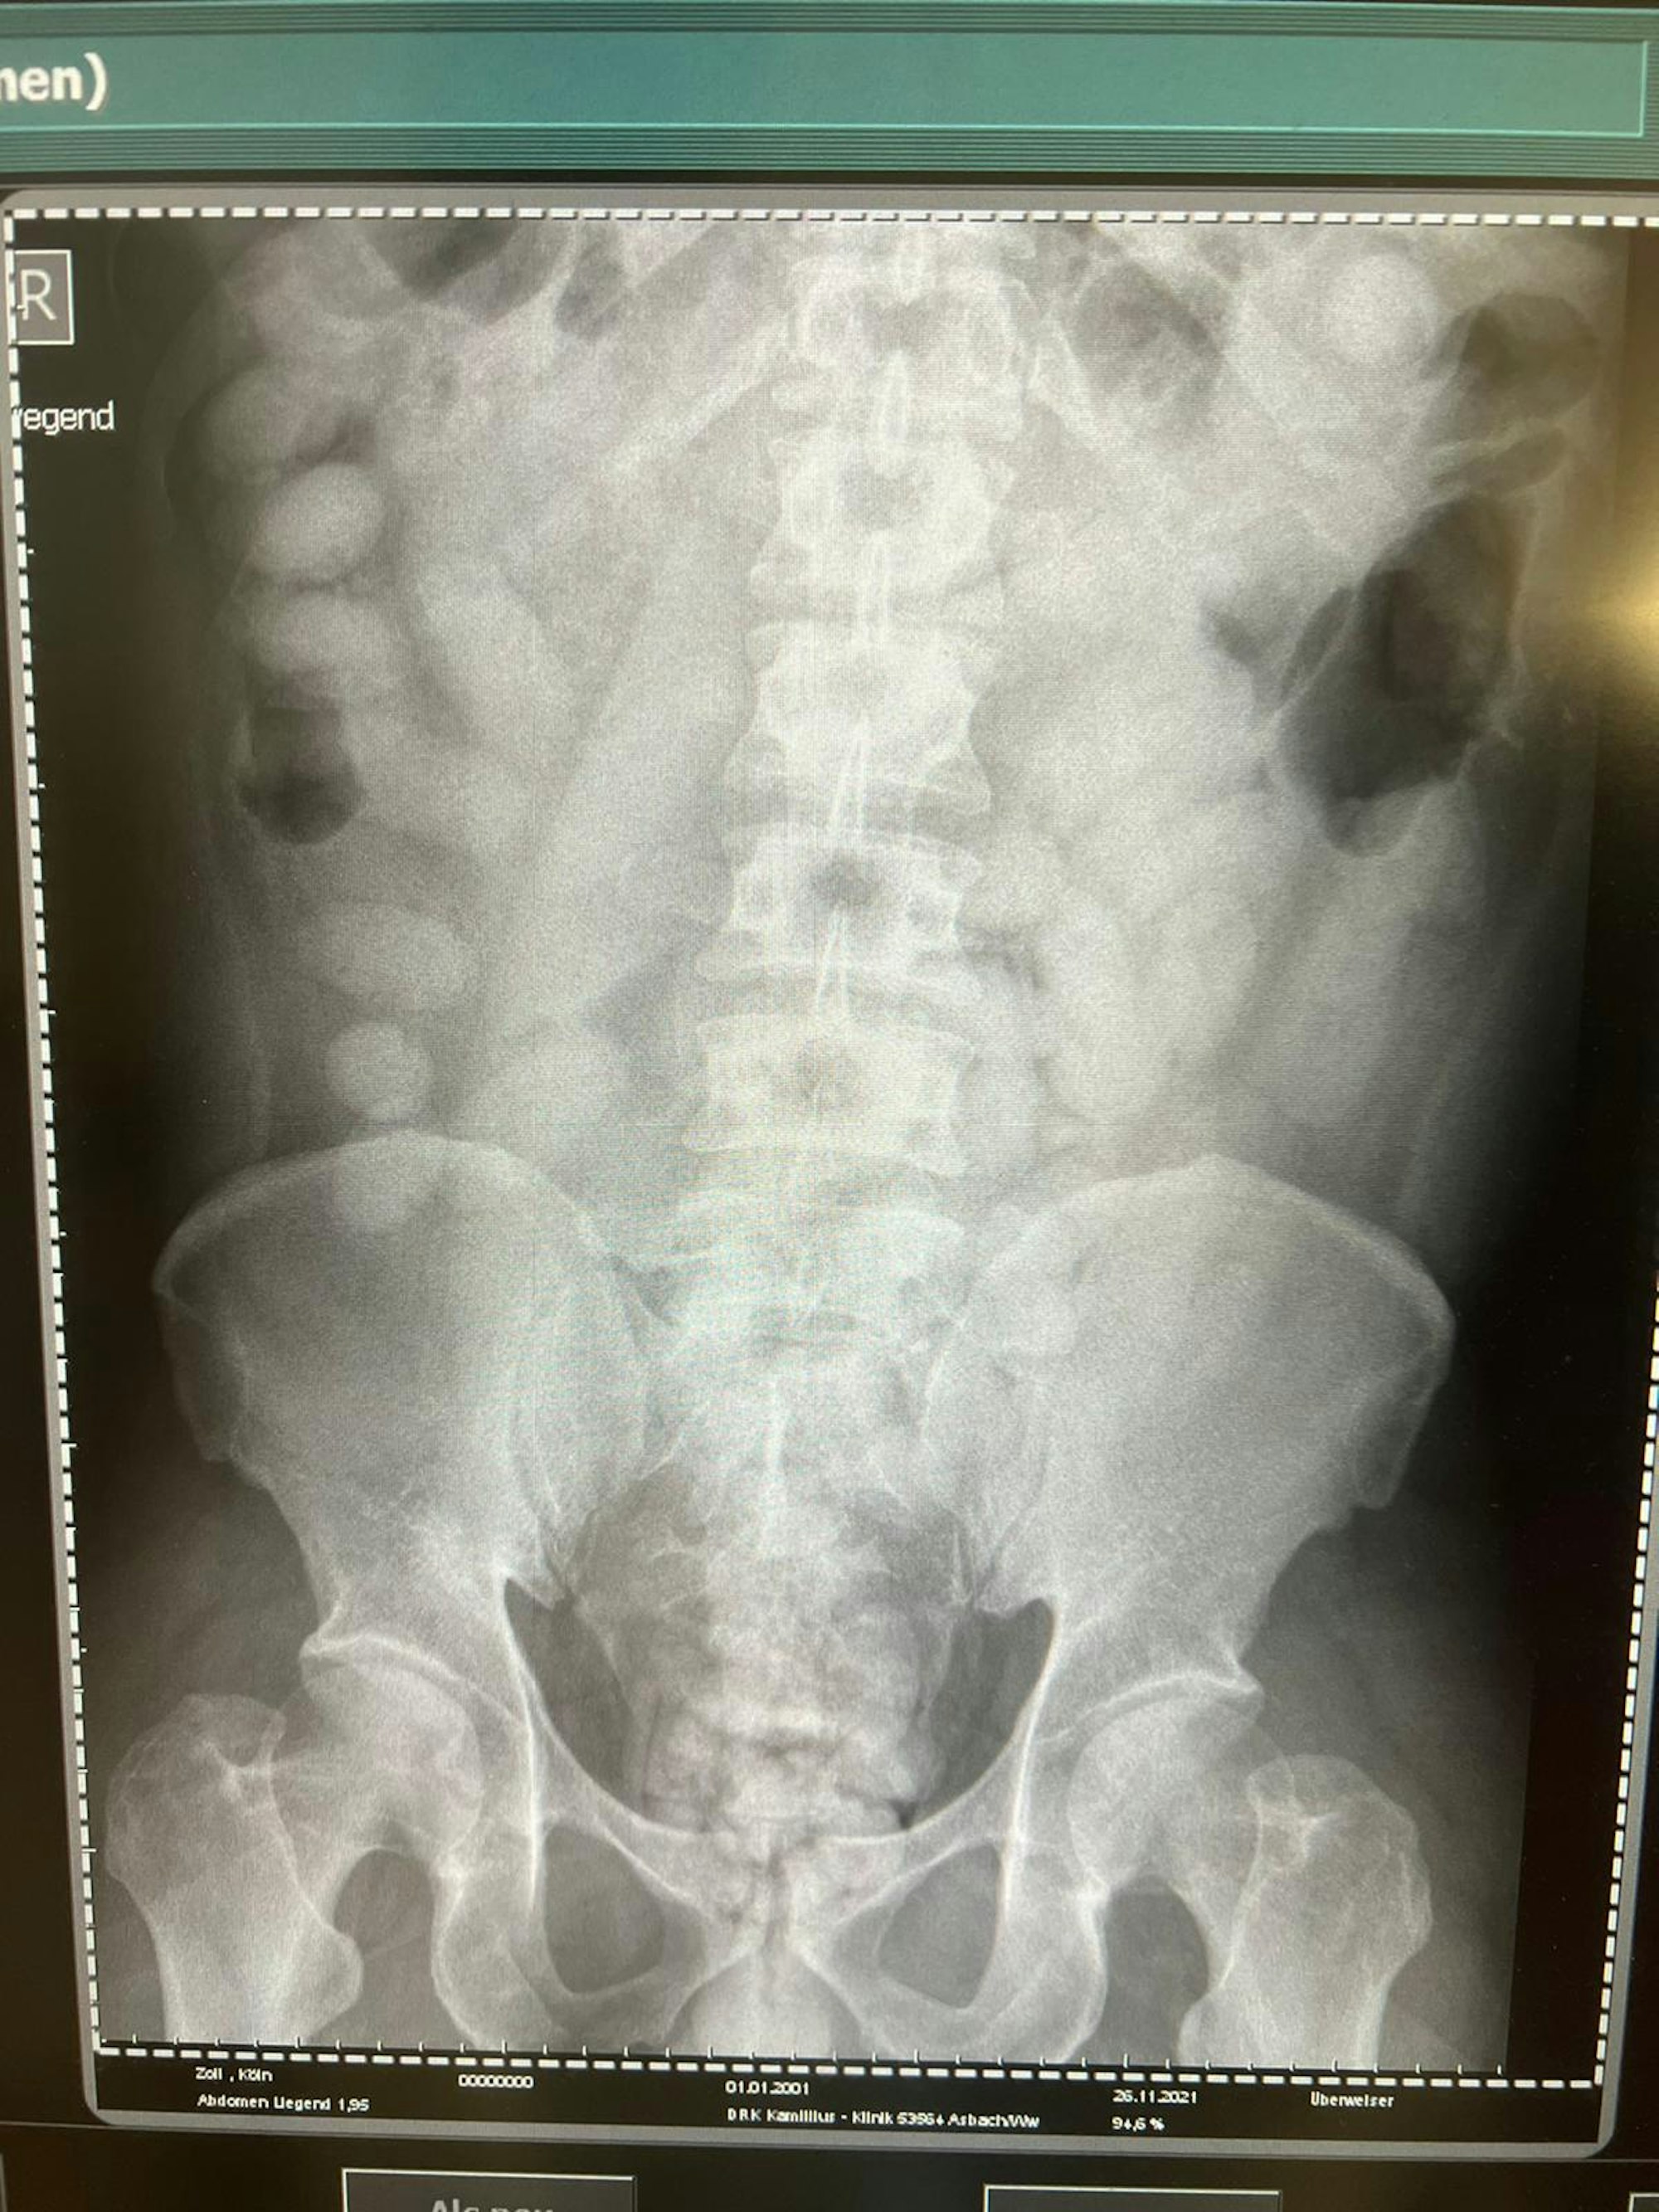

Ende November vorigen Jahres gelang den Kölner Fahndern ein „trauriger Rekord“, wie Ahland es nennt: Genau ein Kilo und acht Gramm Kokain fanden sie im Körper eines 39-jährigen Nigerianers, zusammengepresst in 72 Bodypacks – eine größere Menge Drogen haben die Kölner Ermittler bislang noch nie bei einem Körperschmuggler sichergestellt. „Die Röntgenaufnahme in einem Krankenhaus bestätigte letztendlich den Verdacht“, berichtet Ahland. „Der komplette Magen-Darm-Trakt des Mannes war voll mit Drogenpäckchen.“

Auf dem Röntgenbild sind links kleine, ovale Bodypacks mit Rauschgift zu erkennen